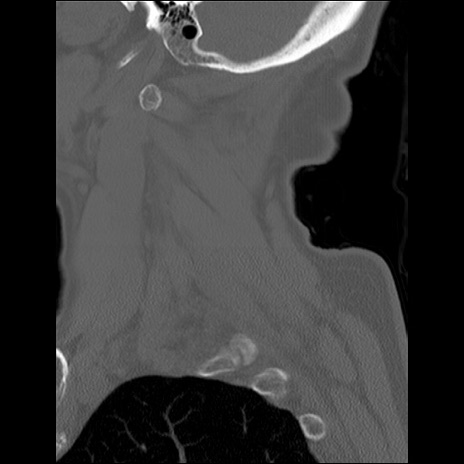

症例48 頚椎CT(矢状断像)

頚椎CT